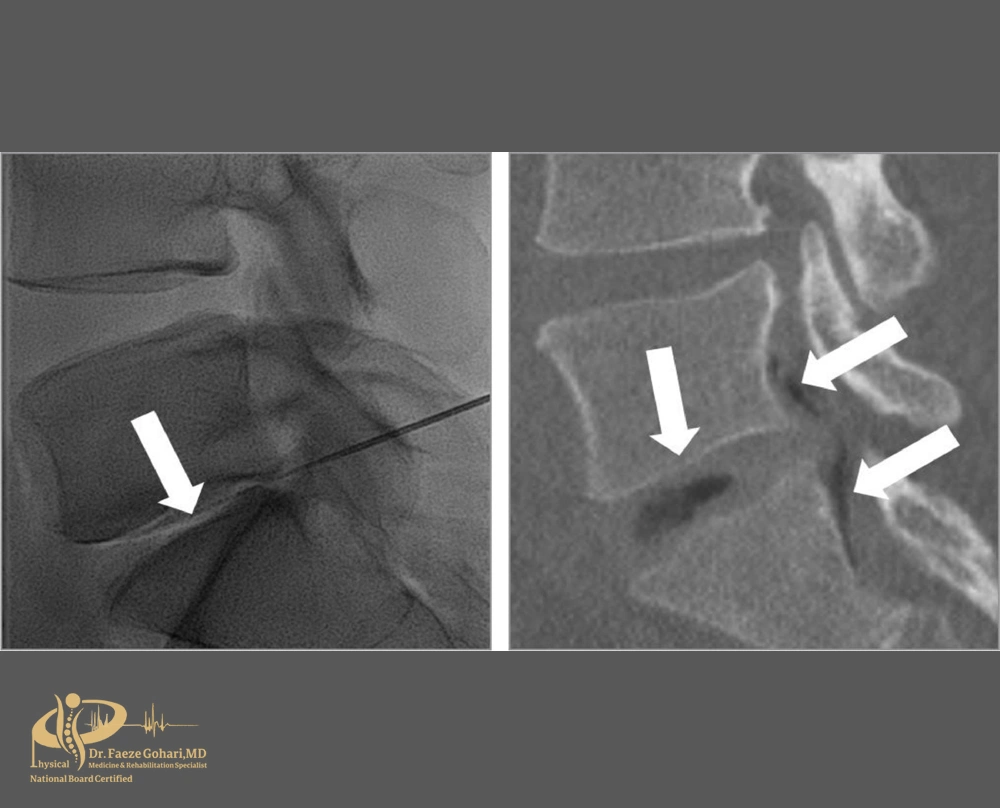

اوزون تراپی برای دیسک کمر معمولاً به دو روش اصلی انجام میشود: تزریق مستقیم به داخل دیسک یا تزریق در ناحیه اطراف و نزدیک به دیسک. موفقیت این درمان تا حد زیادی به انتخاب صحیح روش تزریق بر اساس MRI کمر بستگی دارد.

گاز اوزون نیز در همان لحظه، از طریق دستگاه تخصصی اوزون ساز پزشکی و از اکسیژن خالص تولید شده و با غلظت کنترلشده، بلافاصله در ناحیه مورد نظر تزریق میشود. این تزریق تحت هدایت تصویربرداری فلوروسکوپی انجام میشود تا سوزن بادقت بالا در محل هدف قرار گیرد، بدون آنکه آسیبی به بافتهای اطراف وارد شود.

تزریق مستقیم به داخل دیسک (کوچککردن بیرونزدگی)

دیسککتومی، دقیقترین و مؤثرترین نوع اوزون تراپی برای دیسک کمر است. در این روش اوزون مستقیماً به داخل دیسک آسیبدیده تزریق میشود تا التهاب کاهش یافته و حجم بیرونزدگی کنترل شود. روندی که در بین عموم گاهی بهاشتباه «خشککردن دیسک» نامیده میشود.

تزریق در نزدیکی دیسک (کاهش التهاب اطراف ریشههای عصبی)

در این روش، اوزون به ناحیهای نزدیک به دیسک و اطراف ریشههای عصبی تزریق میشود – نه به داخل خود دیسک. هدف از این تزریق، کاهش التهاب، کاهش فشار عصبی و تسکین دردهای تیر کشنده مانند سیاتیک است.

سوزن بادقت بالا در نزدیکی محل خروج عصب از ستون فقرات قرار میگیرد – در عمقی متفاوت از تزریقهای عضلانی.